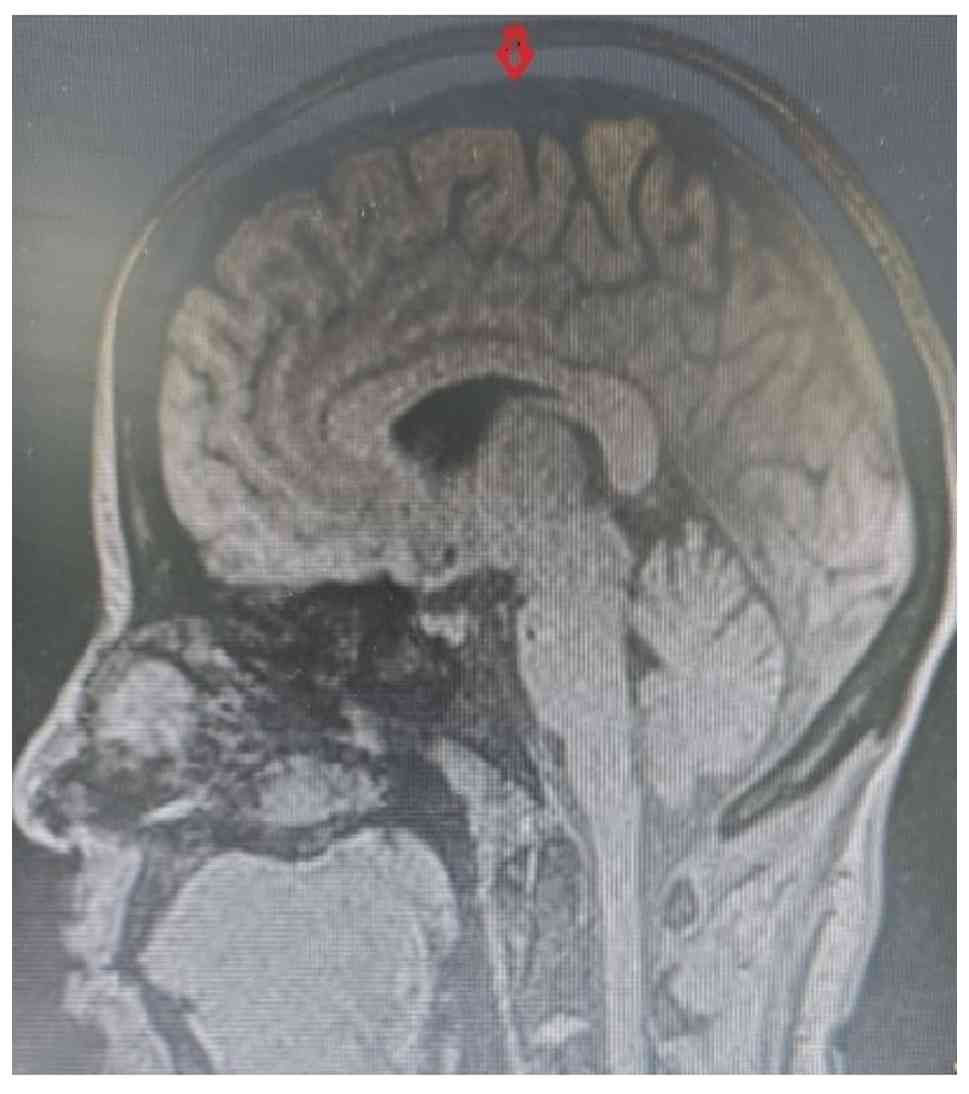

The patient had undergone complete neurological and ophthalmological recovery by June 2024; serial imaging confirmed complete CVST resolution (Fig. 6). Both mother and infant remained healthy, and the patient was advised to seek pre-conceptional counselling when planning any future pregnancies.

Follow-up image. MRI T1-weighted

sagittal view of the brain. The arrow shows normal flow voids in

the superior sagittal sinus. Image was obtained in June 2024.

Figure 6

Follow-up image. MRI T1-weighted sagittal view of the brain. The arrow shows normal flow voids in the superior sagittal sinus. Image was obtained in June 2024.